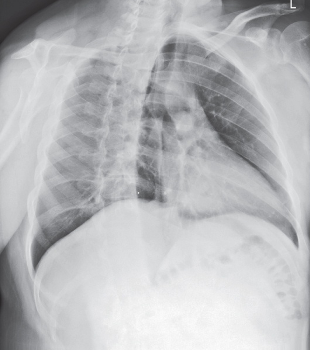

Pneumothorax

collapsed lung

usually only a portion of lung collapses

air pushes on pleural space making it collapse

no lung markings

exposure remains the same